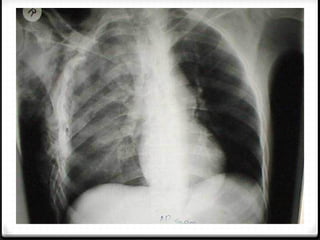

Pneumothoraks

0 Udara pada rongga pleura

0 15%–40% ditemukan pada trauma thoraks

0 Ruptur alveoli karena ada tekanan meninggi secara tiba-tiba

pada intrathorakal akibat trauma dengan atau tanpa fraktur

costae

0 Radigrafi polos >>

0 ± 10% tidak dapat dievaluasi dengan radiografi polos  CT scan

Hidropneumothoraks kanan